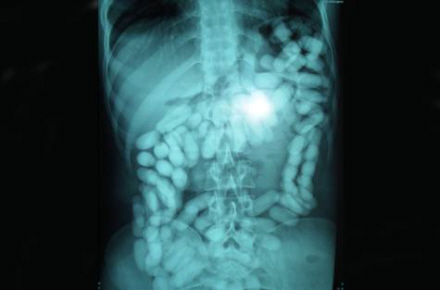

Det er tydeligt at se poserne med narko på scanningsbilleder